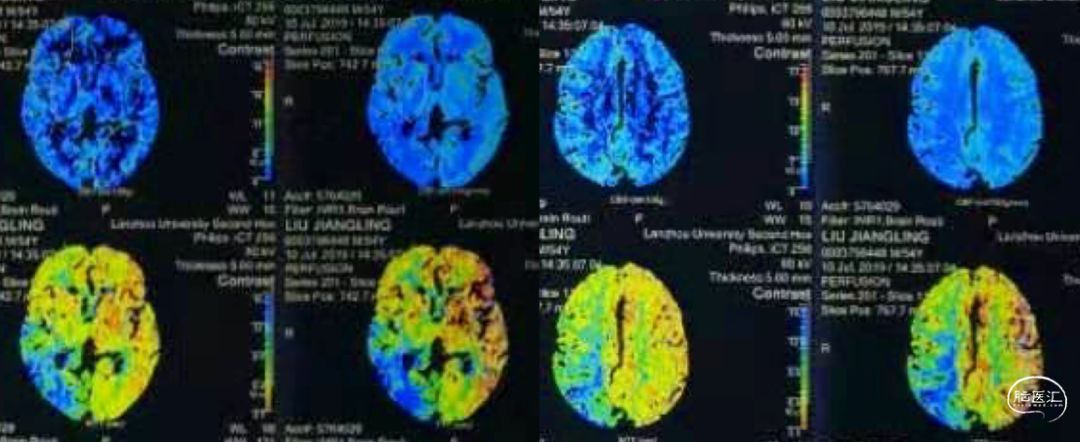

入院后,我们补充了几项检查,包括灌注、高分辨核磁,并复查造影。灌注提示:右侧半球CBF降低、TTP和MTT延长。但由于左侧MCA狭窄,所以并不非常显著。

当地医院灌注检查提示:右侧半球灌注不足。

入院后我们首先对其进行超声检查,结果有点出乎我们的预料——极重度狭窄,而非闭塞![]() ,难道当地造影结果有误?